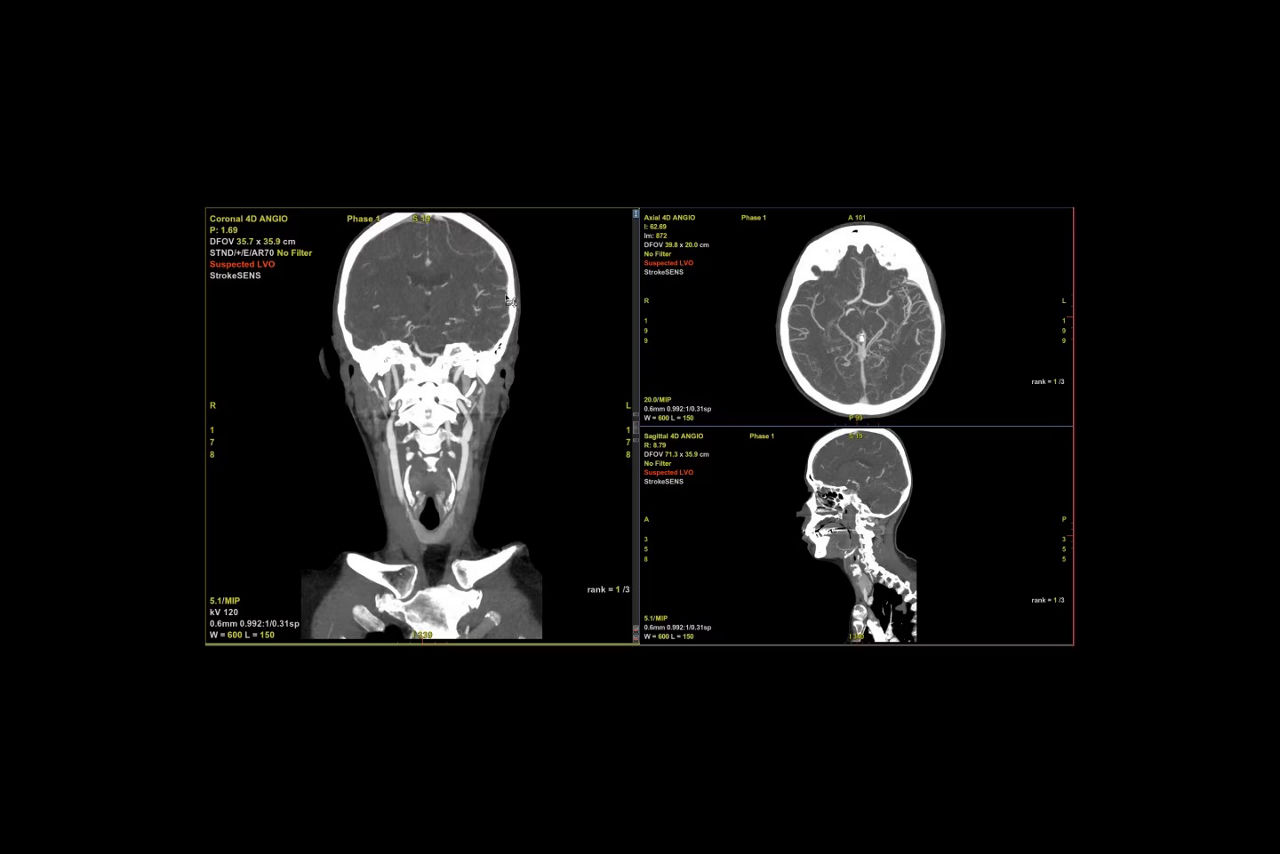

• StrokeSENS LVO²

StrokeSENS LVO uses AI to identify Large Vessel Occlusion (LVO) on CT Angiography.

• StrokeSENS LVO automatically notifies the stroke team of suspected LVO cases within minutes of receiving the CTA image, supporting early engagement of the stroke team.

• In the case a LVO is detected, Suspected LVO is written onto the input DICOM image (CTA or 1st phase of mCTA) and results are automatically included in the email notification, helping notify the stroke team of the time-sensitive case.